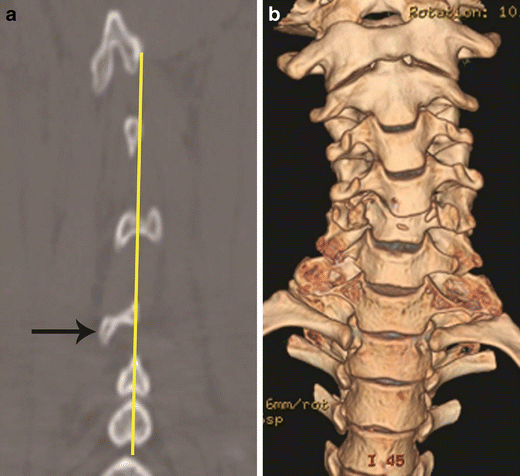

Rotational vector and deformity. a Posterior coronal CT image shows focal deviation of the C5 spinous process (arrow)—suggested by the interspinous line not passing through the rotated C5 spinous process. b Three-dimensional volume rendered coronal image shows rotational deformity of the C5/C6 vertebrae